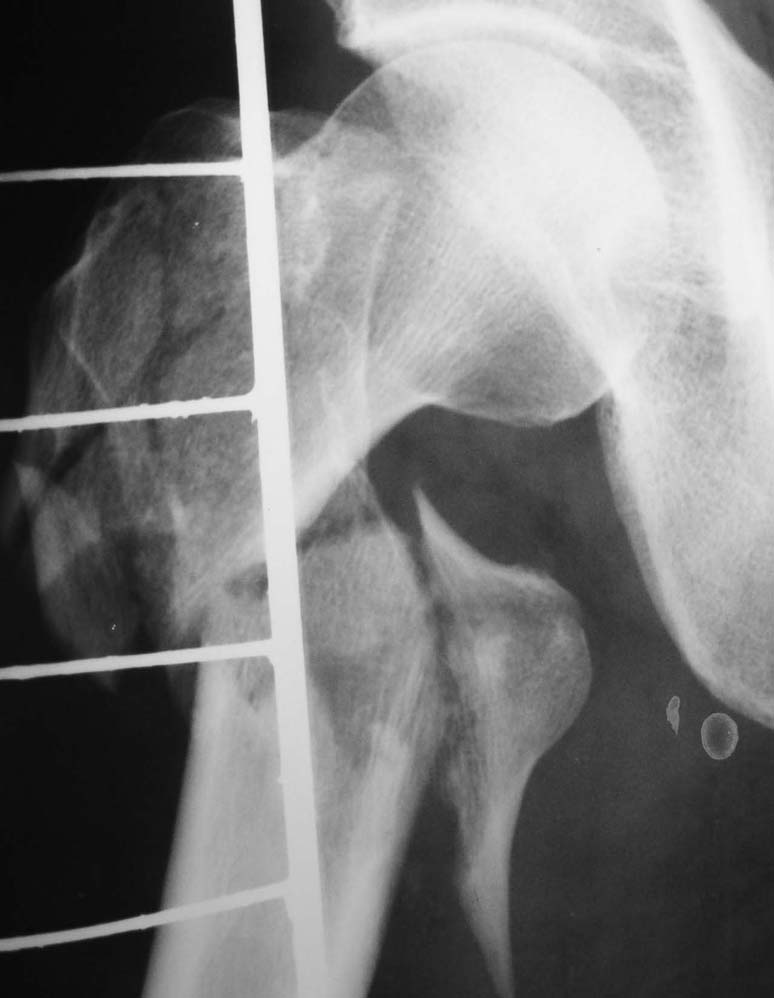

Другое наблюдение:Мужчина, 1957 г.р. Травма в результате ДТП 12.09.04г.

Диагноз: Закрытый оскольчатый подвертельный перелом правой бедренной кости со смещением отломков, оскольчатый перелом большого вертела, отрывной перелом малого вертела.Сопутствующие заболевания: Язвенная болезнь желудка, ремиссия.